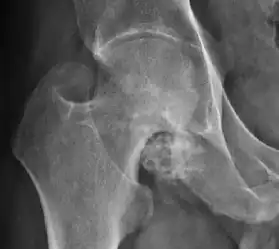

Plain radiography allows us to categorize the hip as normal or dysplastic or with impingement signs (pincer, cam, or a combination of both). Besides these, pathologic processes like osteoarthritis, inflammatory diseases, infection, or tumors can also be identified (Figure 1).[1]

Figure 1.

Osteoarthritis

In adults, one of the main indications for radiographs is the detection of osteoarthritic changes (Figure 1(e)). Nevertheless, radiographs usually detect advanced osteoarthritis that can be graded according to the Tönnis classifications. The grading system ranges from 0 to 3, where 0 shows no sign of osteoarthritis. Intermediate grade 1 shows mild sclerosis of the head and acetabulum, slight joint space narrowing, and marginal osteophyte lipping. Grade 2 presents with small cysts in the femoral head or acetabulum, moderate joint space narrowing, and moderate loss of sphericity of the femoral head. Grade 3 is the severest form of osteoarthritis, which manifests as severe narrowing of the joint space, large subchondral cyst with productive bone changes that may lead to deformity of the bone components of the joint, while secondary osteoarthritis due to calcium pyrophosphate deposition can be diagnosed when calcification of hyaline cartilage and fibrocartilage is detected.[1]

There are other pathological conditions that can affect the hip joint and radiographs help to make the appropriate diagnosis. Acute bacterial septic arthritis can be diagnosed by radiographs when a fast regional osteoporosis and destructive monoarticular process develops (Figure 1(f)). In case of tuberculous or brucella arthritis it is manifested as a slow progressive process, and diagnosis may be delayed.[1]

Synovial chondromatosis can be confidently diagnosed by X-ray when calcified cartilaginous chondromas are seen. However, other synovial proliferative processes, such as pigmented villonodular synovitis, require MRI for accurate diagnosis, although noncalcified synovitis can be suspected in radiographs by indirect signs, such as soft tissue swelling and/or erosions in the femoral head, femoral neck, or acetabulum (Figure 7).[1]